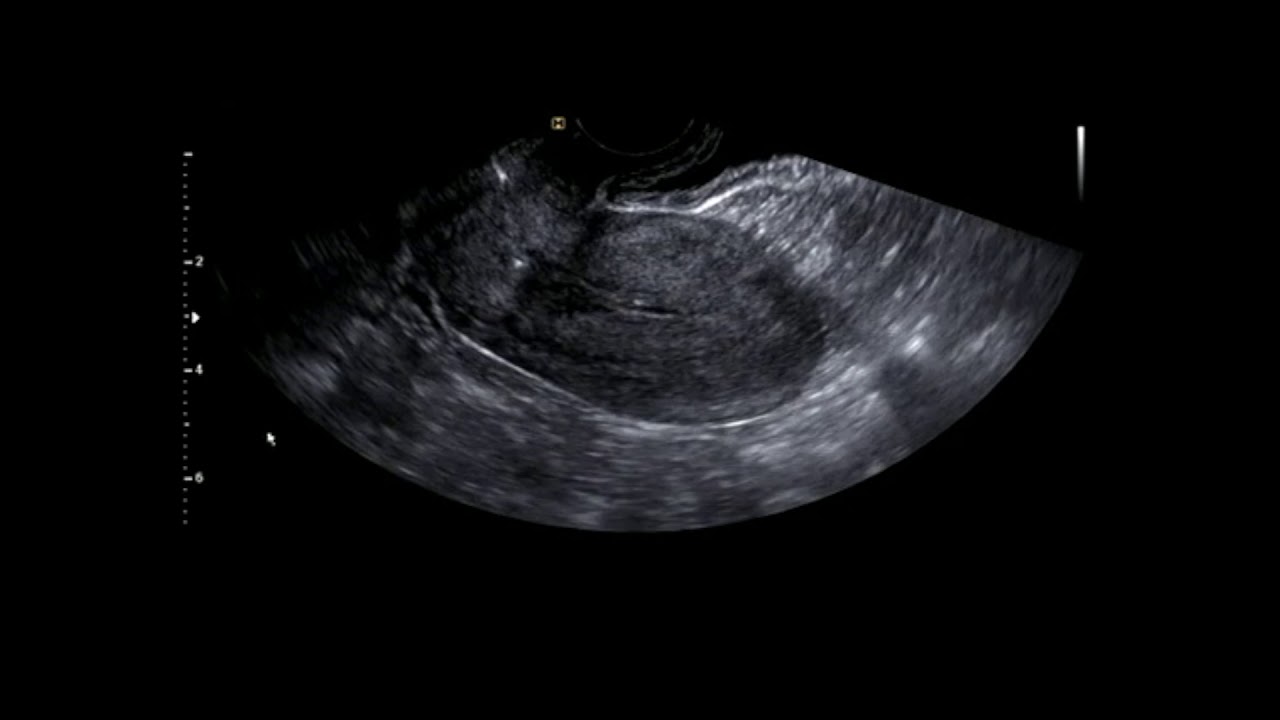

정상 자궁과 난소의 초음파 동영상

안녕하세요. 마포구 동교동에 개원하고 있는 진오비 산부인과 원장 심상덕입니다. 출산 후 6주 산후 진찰시의 초음파 동영상입니다. 임신으로부터 거의 회복된 정상 자궁과 정산 난소의 모습입니다. 영상에 제 목소리가 들어가 있어서 따로 설명 자막을 달지는 않았습니다. 영상은 환자분께 동의를 받고 올렸습니다.